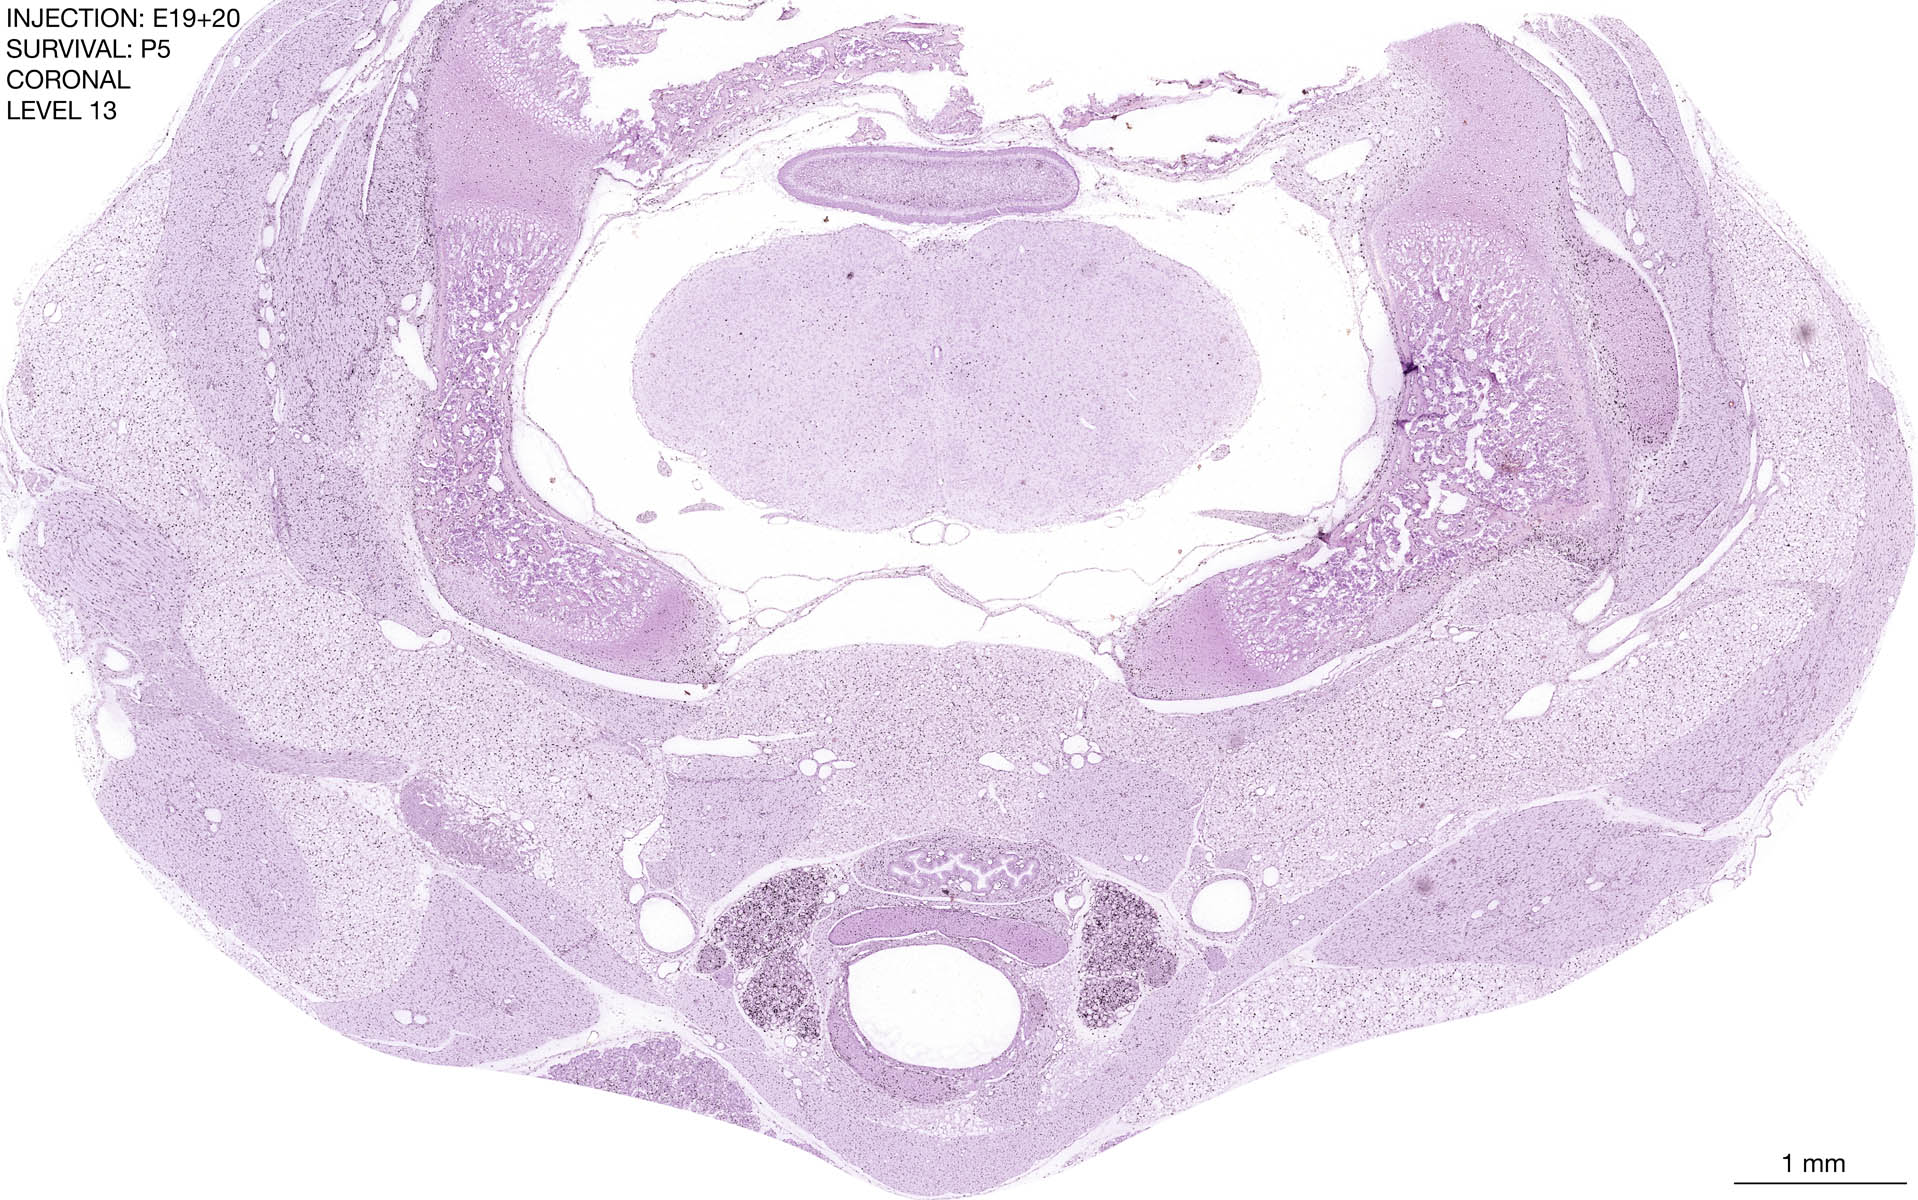

E19+20 P5 Survival The images below are from the brain of a rat that was exposed to tritiated thymidine on E19+20 and survived to P5. Download: Large | High Res Download: Large | High Res Download: Large | High Res Download: Large | High Res Download: Large | High Res Download: Large | High Res Download: Large | High Res Download: Large | High Res Download: Large | High Res Download: Large | High Res Download: Large | High Res Download: Large | High Res Download: Large | High Res Download: Large | High Res Download: Large | High Res Download: Large | High Res Download: Large | High Res Download: Large | High Res Download: Large | High Res Download: Large | High Res Download: Large | High Res Download: Large | High Res Download: Large | High Res Download: Large | High Res Download: Large | High Res Download: Large | High Res Download: Large | High Res Download: Large | High Res